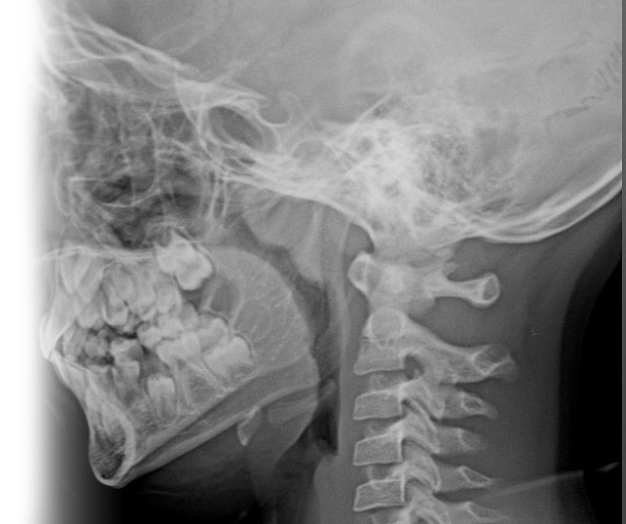

Рентгенография носоглотки – важный метод прицельного исследования, который позволяет оценить состояние носоглотки и ее просвет.

Диагностическая услуга выполняется в одной проекции.

Показания для проведения рентген носоглотки:

• нарушение носового дыхания;

• воспалительные процессы, деформации и травмы носоглотки;

• подозрение на наличие аденоидных вегетаций.